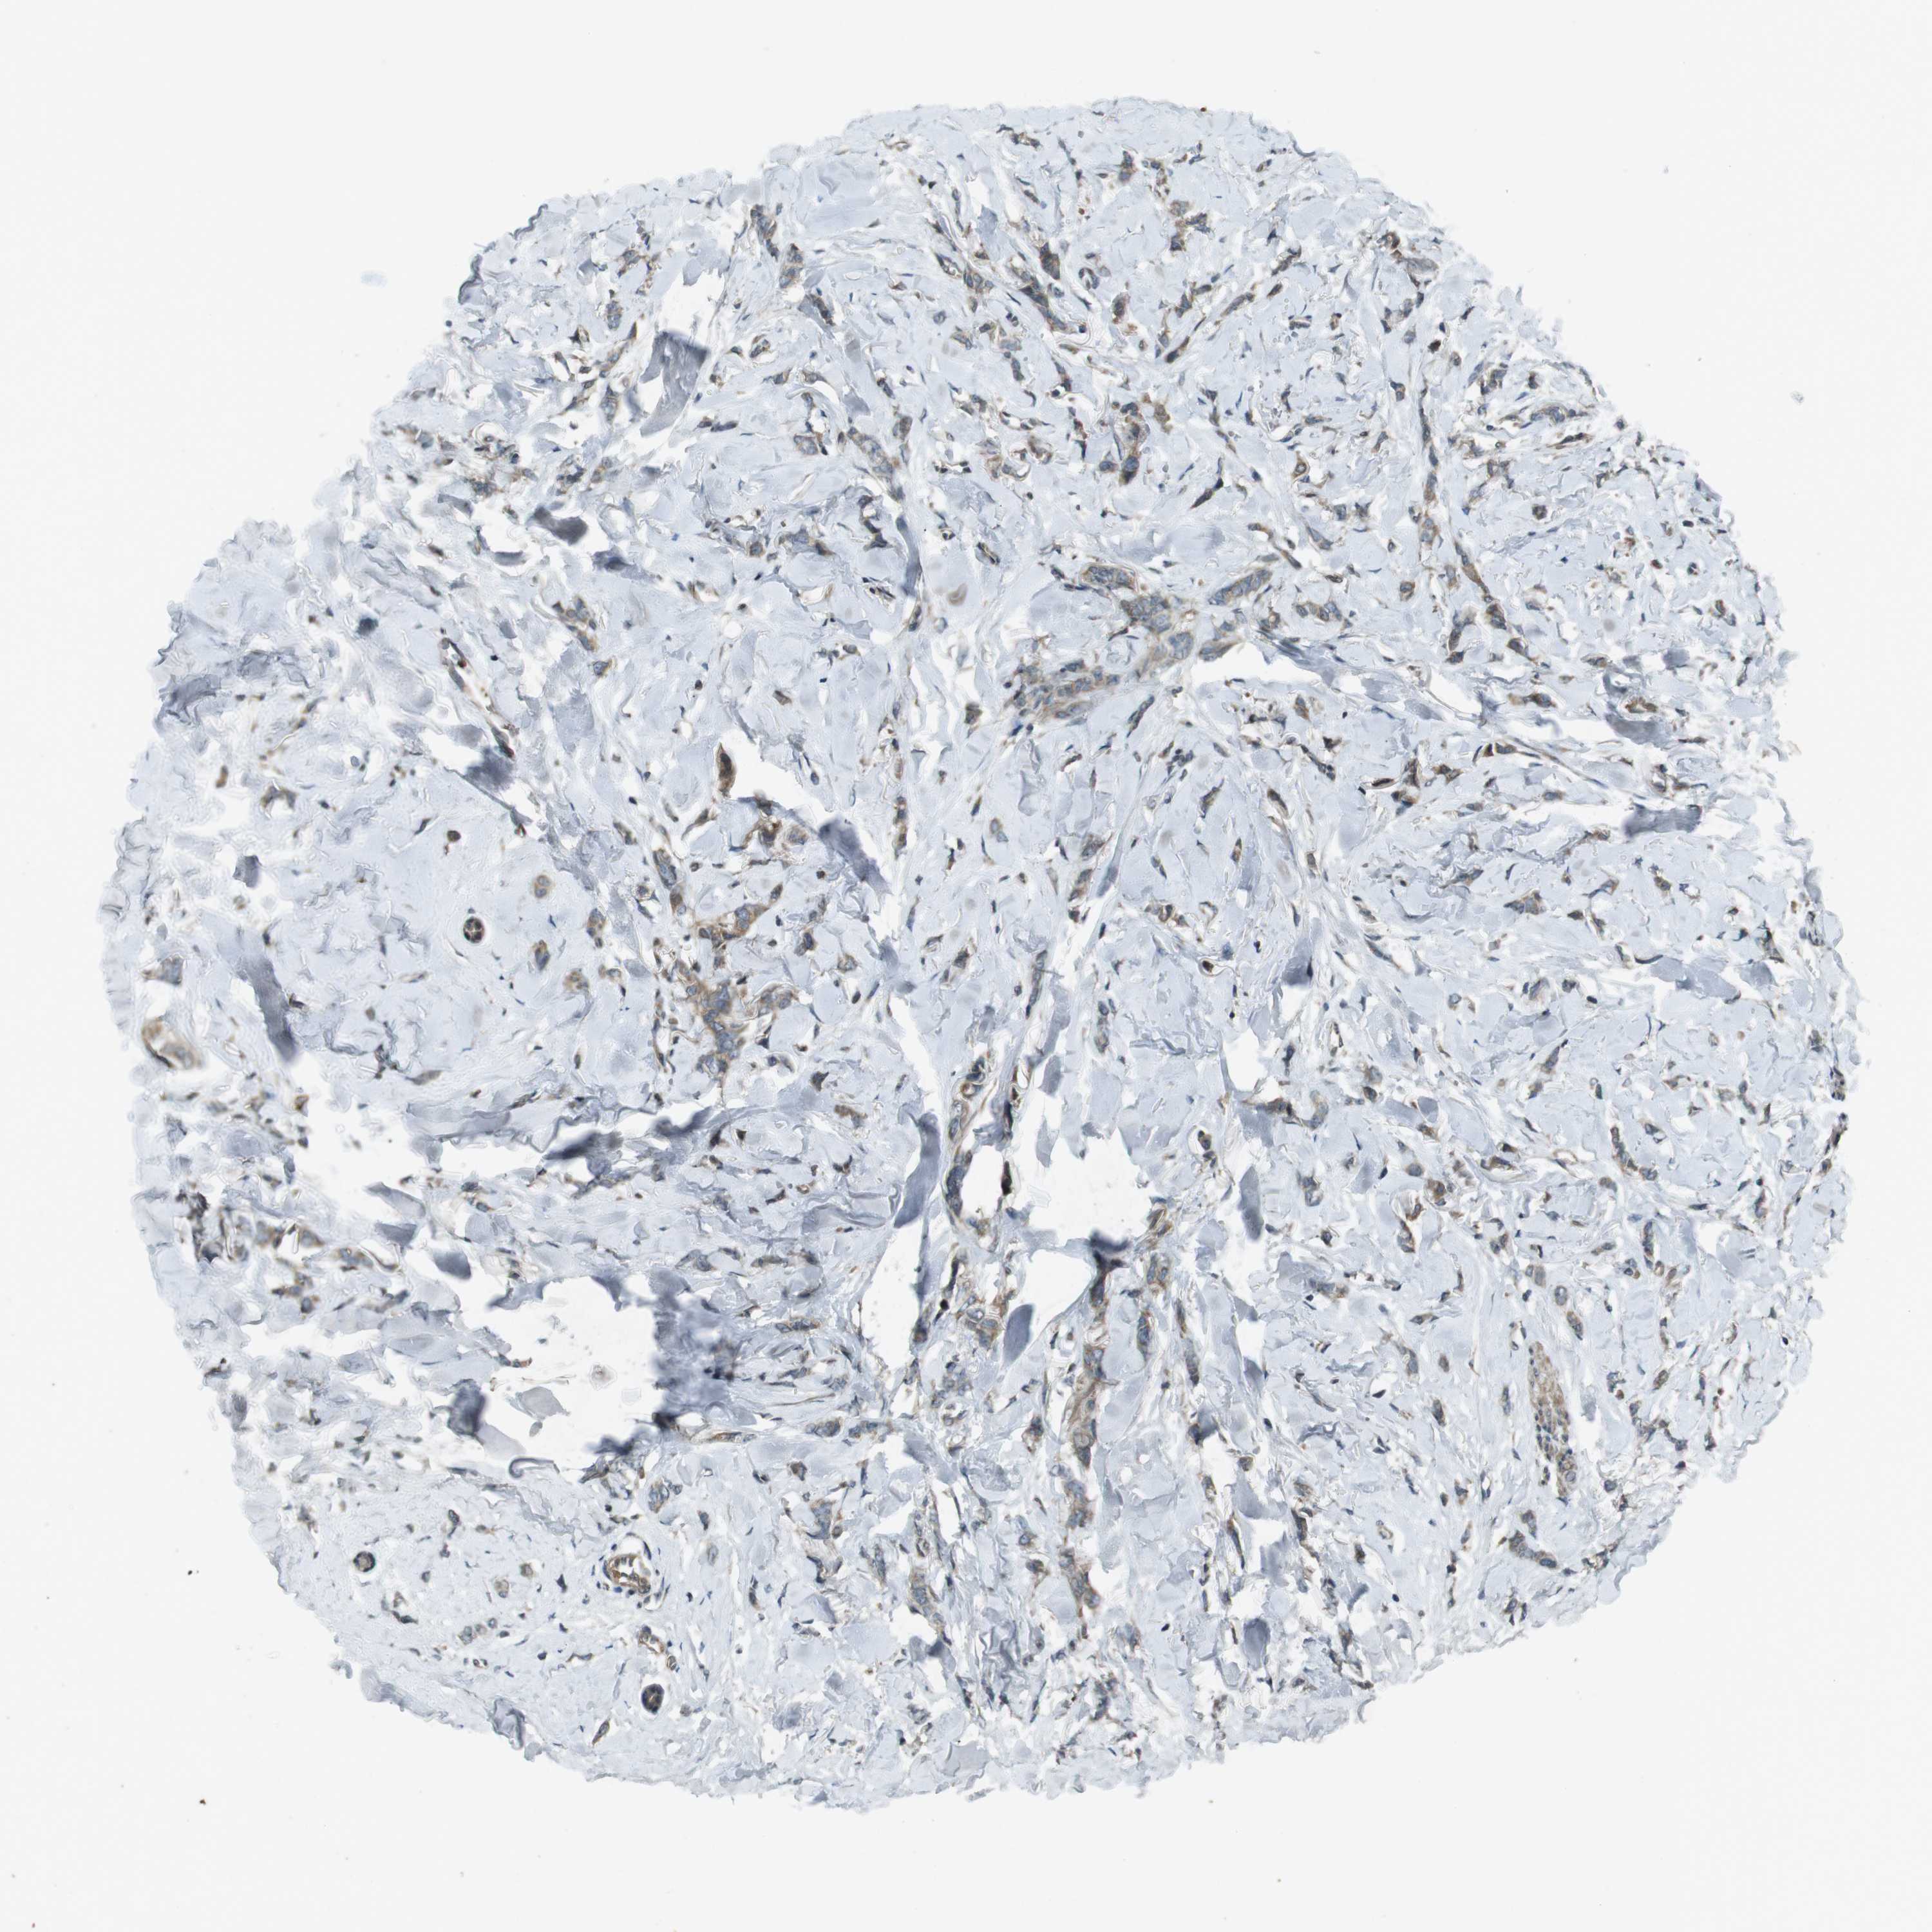

CANCER BREAST CANCER Show tissue menu

BRCA TCGA BRCA VALIDATION PROTEIN EXPRESSION